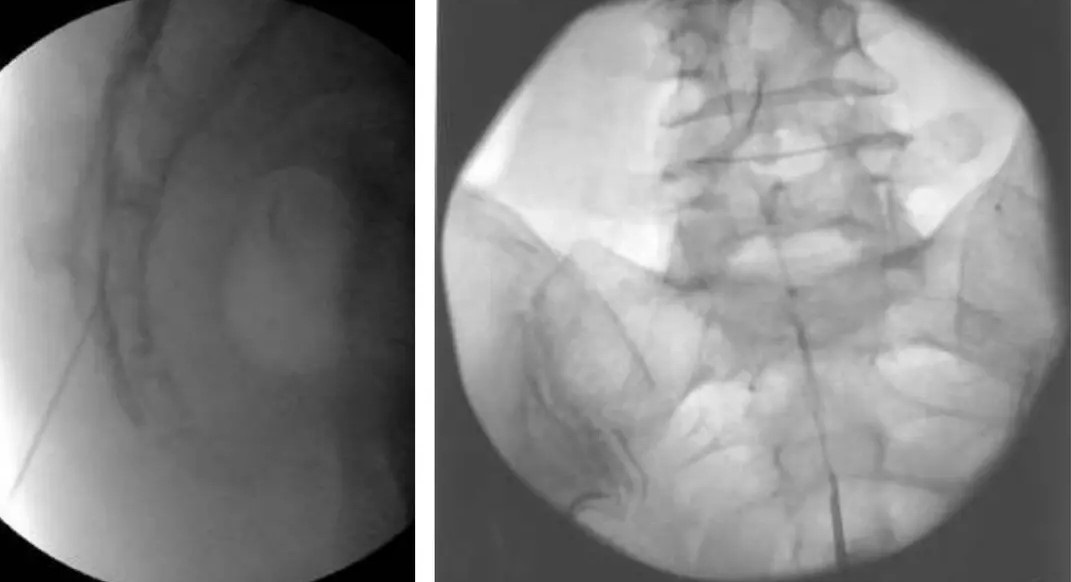

Στην ουραία επισκληρίδιο έγχυση υπό ακτινοσκοπική καθοδήγηση, εισάγεται ένας καθετήρας μέσω του ιερού τρήματος και προωθείται έως το επίπεδο στης κατώτερης οσφυϊκής μοίρας, όπου γίνεται η έγχυση διαλύματος τοπικού αναισθητικού και στεροειδούς.

Τι είναι η Επισκληριδιοσκόπηση

Πρόκειται για μια ελάχιστα επεμβατική τεχνική λύσης μετεγχειρητικών συμφύσεων με εισαγωγής ενός εύκαμπτου ενδοσκοπίου στην οσφυϊκή μοίρα μέσω του ιερού τρήματος. Με χρήση διαλύματος υαλουρονιδάσης και φυσιολογικού ορού επιτυγχάνεται οι λύση συμφύσεων, με σύγχρονη απελευθέρωση των νευρικών δομών.